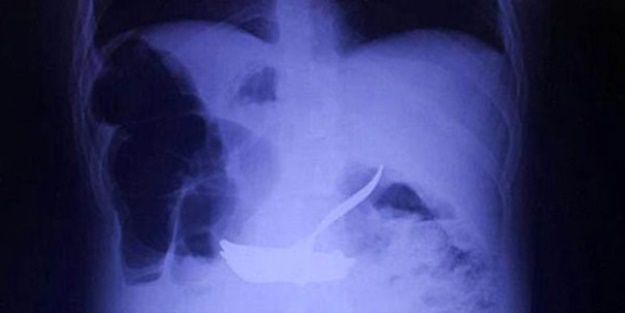

Antalya'nın Manavgat İlçesi'nde oturan down sendromlu 23 yaşındaki Ali Güven'in midesinden, ameliyatla 6 çivi ve 4 çatal çıkarıldı.

10 gün önce mide bulantısı, kusma ve karın ağrısı şikayetleriyle Manavgat Devlet Hastanesi'ne başvuran down sendromlu Ali Güven'in midesinde çok sayıda yabancı cisim görülmesi üzerine Antalya'ya sevk edildi. Ali Güven'in midesindeki 6 çivi ve 4 çatal, Antalya Atatürk Devlet Hastanesi Genel Cerrahi Uzmanı Opr. Dr. Murat İnan tarafından, 2 saat süren operasyonla, yemek borusu ve mide üst bölümüne müdahale edilerek çıkartıldı.

Opr. Dr. İnan, toplu iğne ve para gibi küçük yabancı cisimlerin kendiliğinden atılabildiğini belirterek, "Ama bu büyüklükteki yabancı cisimler yemek borusu ile mide üst kısmında kaldığı için, yaşanan son olayda olduğu gibi ancak ameliyatla alabiliyoruz. Hastamızın midesinden 4'ü çatal, 6'sı çivi olmak üzere 10 cisim çıkardık" dedi.

Hastanın yuttuğu 6 çivinin daha eski tarihli olduğunu söyleyen Opr. Dr. Murat İnan, "Çivilerin yutulma zamanının üç ay olduğunu düşünüyorum. Çatallarla ilgili bir tahmin yapmam uygun değil ama çivilerin daha eski olduğunu ifade edebilirim. Eğer müdahale edip yabancı cisimleri çıkarmasaydık mideyi delip organ tahribine neden olacaktı" dedi.